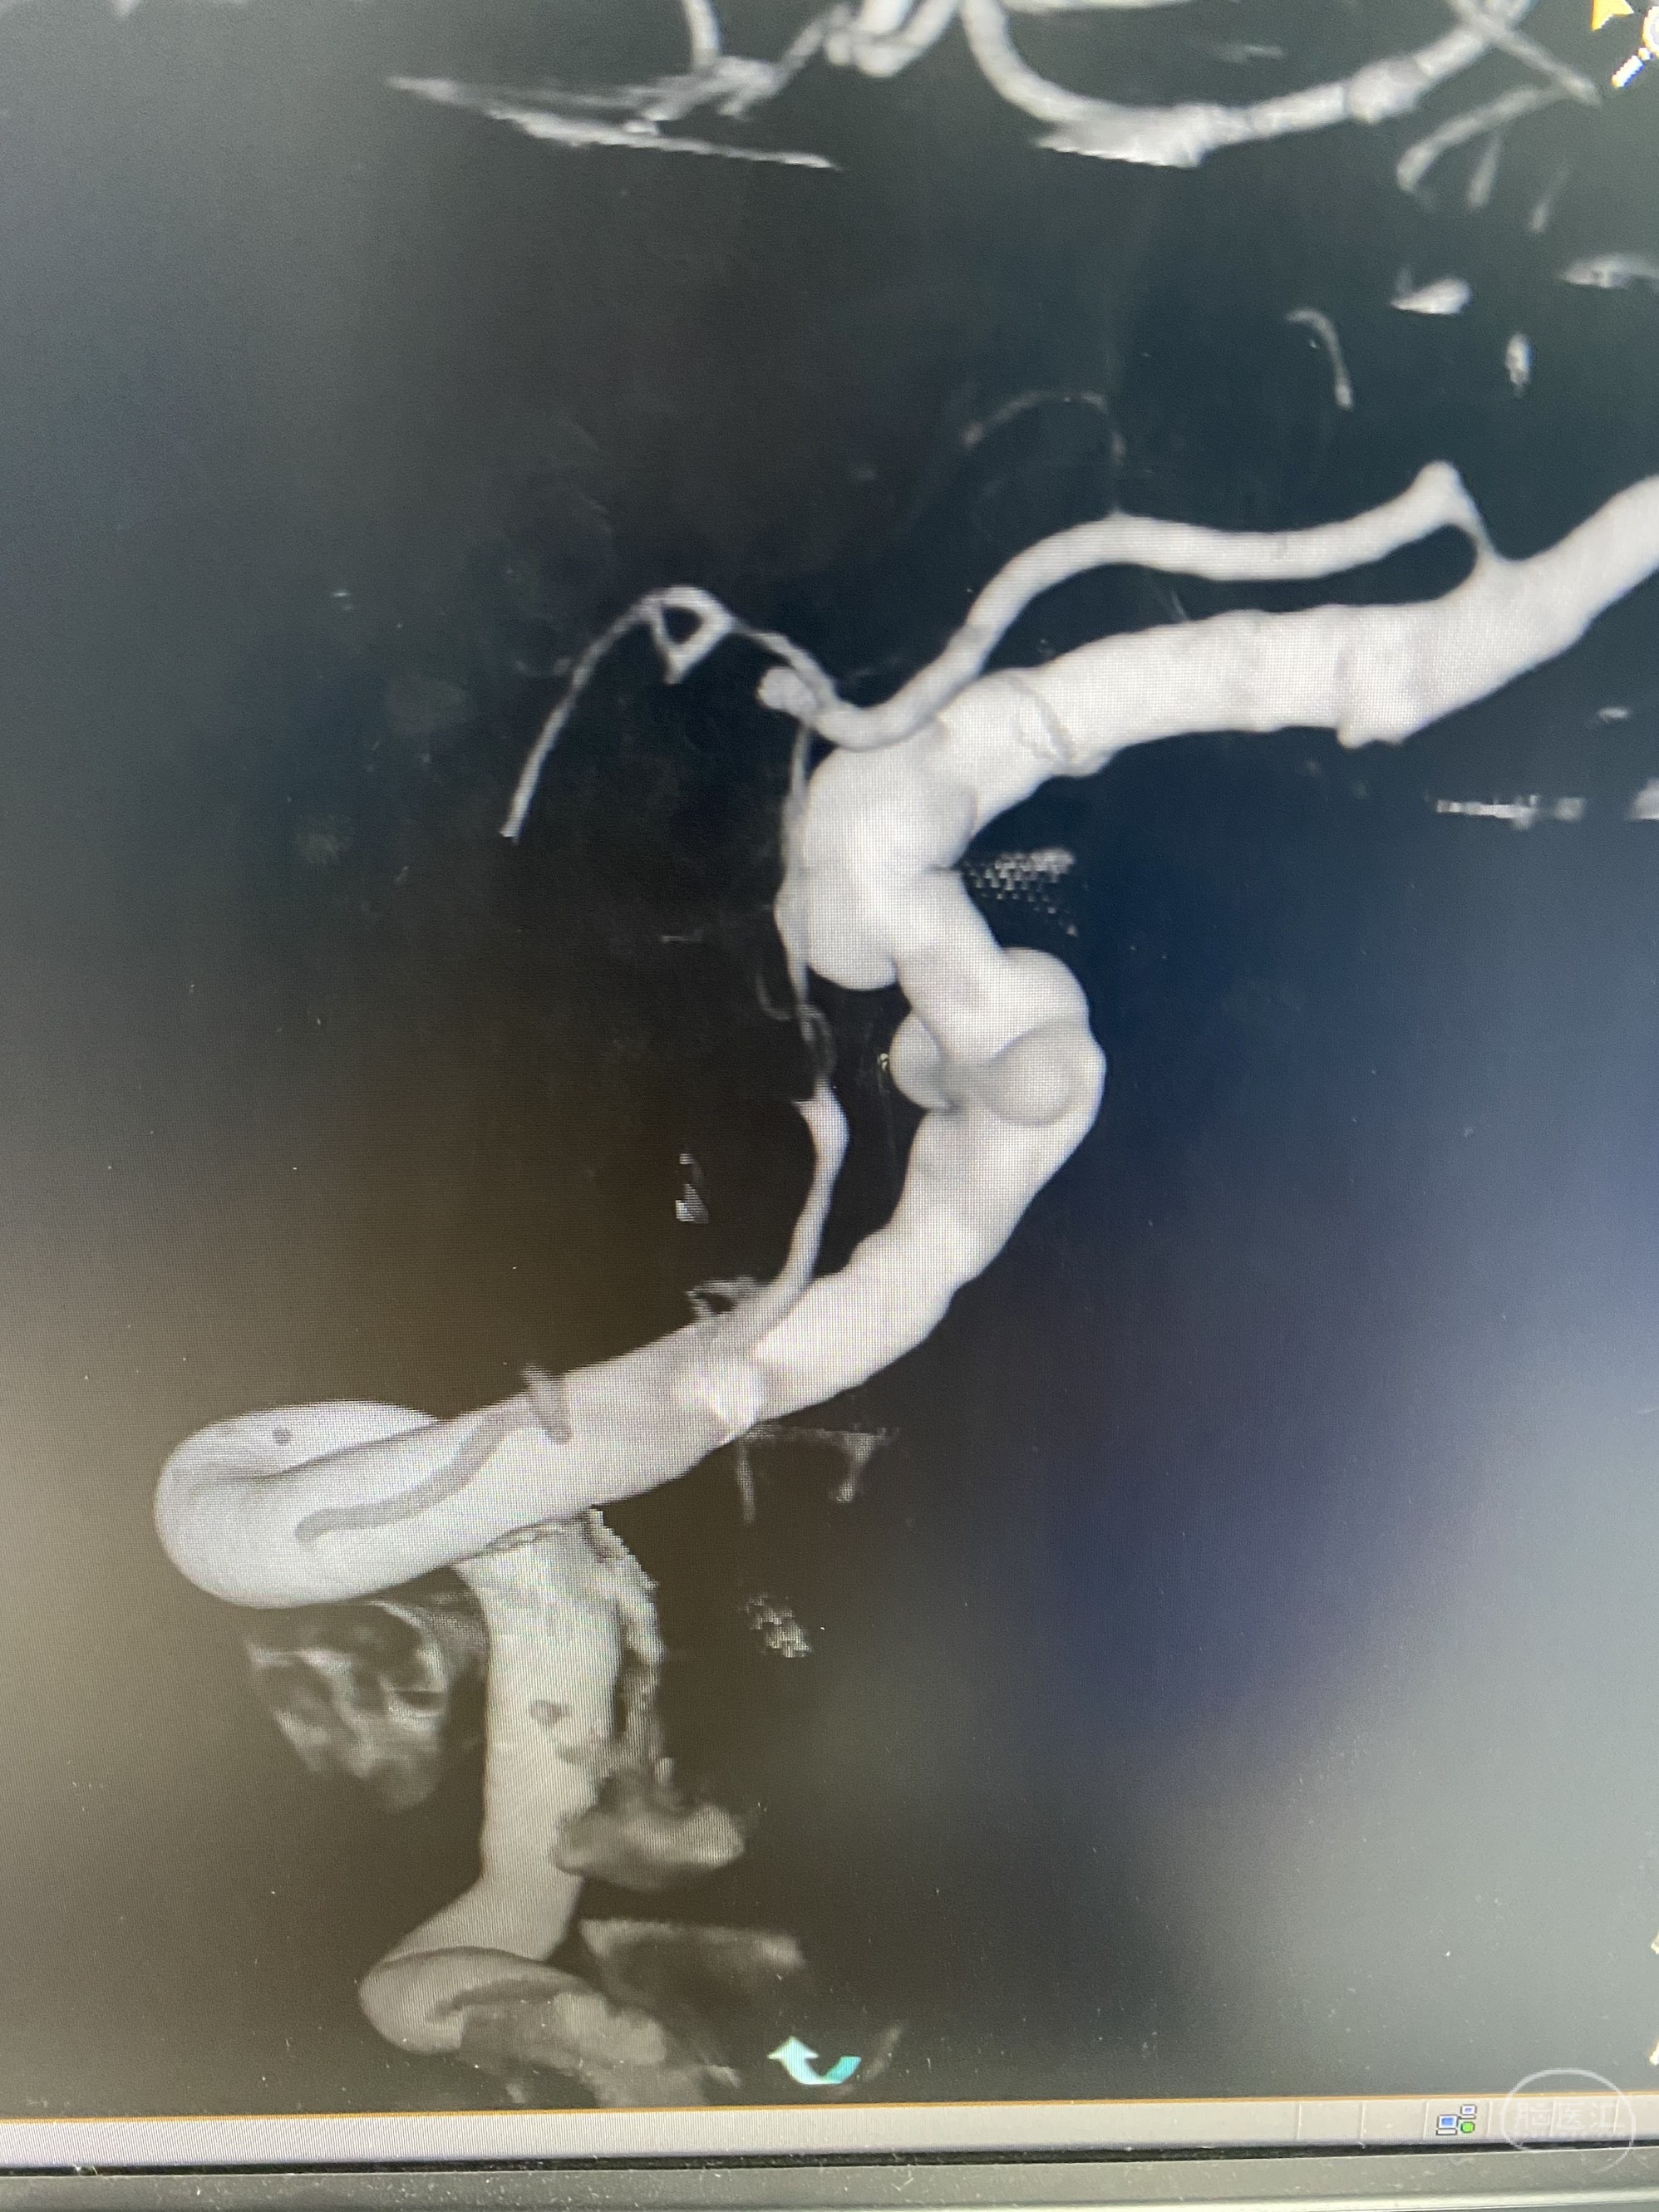

椎动脉颅内段多发夹层动脉瘤伴载瘤动脉狭窄pipeline flex植入

今日手术,TJG,M62Y,一期左侧颈动脉狭窄支架植入,二期椎动脉V4段多发夹层动脉瘤伴狭窄,常规支架辅助栓塞方法复杂又危险,血流导向装置植入快捷又安全。南阳市中心医院神经内科脑血管病介入团队pipeline flexFD植入两人导师资格。